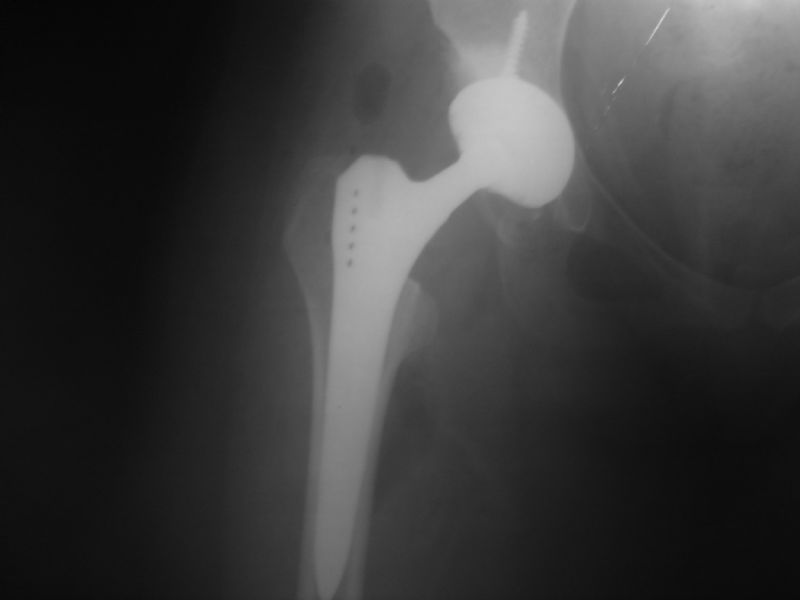

Total Kalça Protezi

Total Kalça Protezi Örnek Olgular